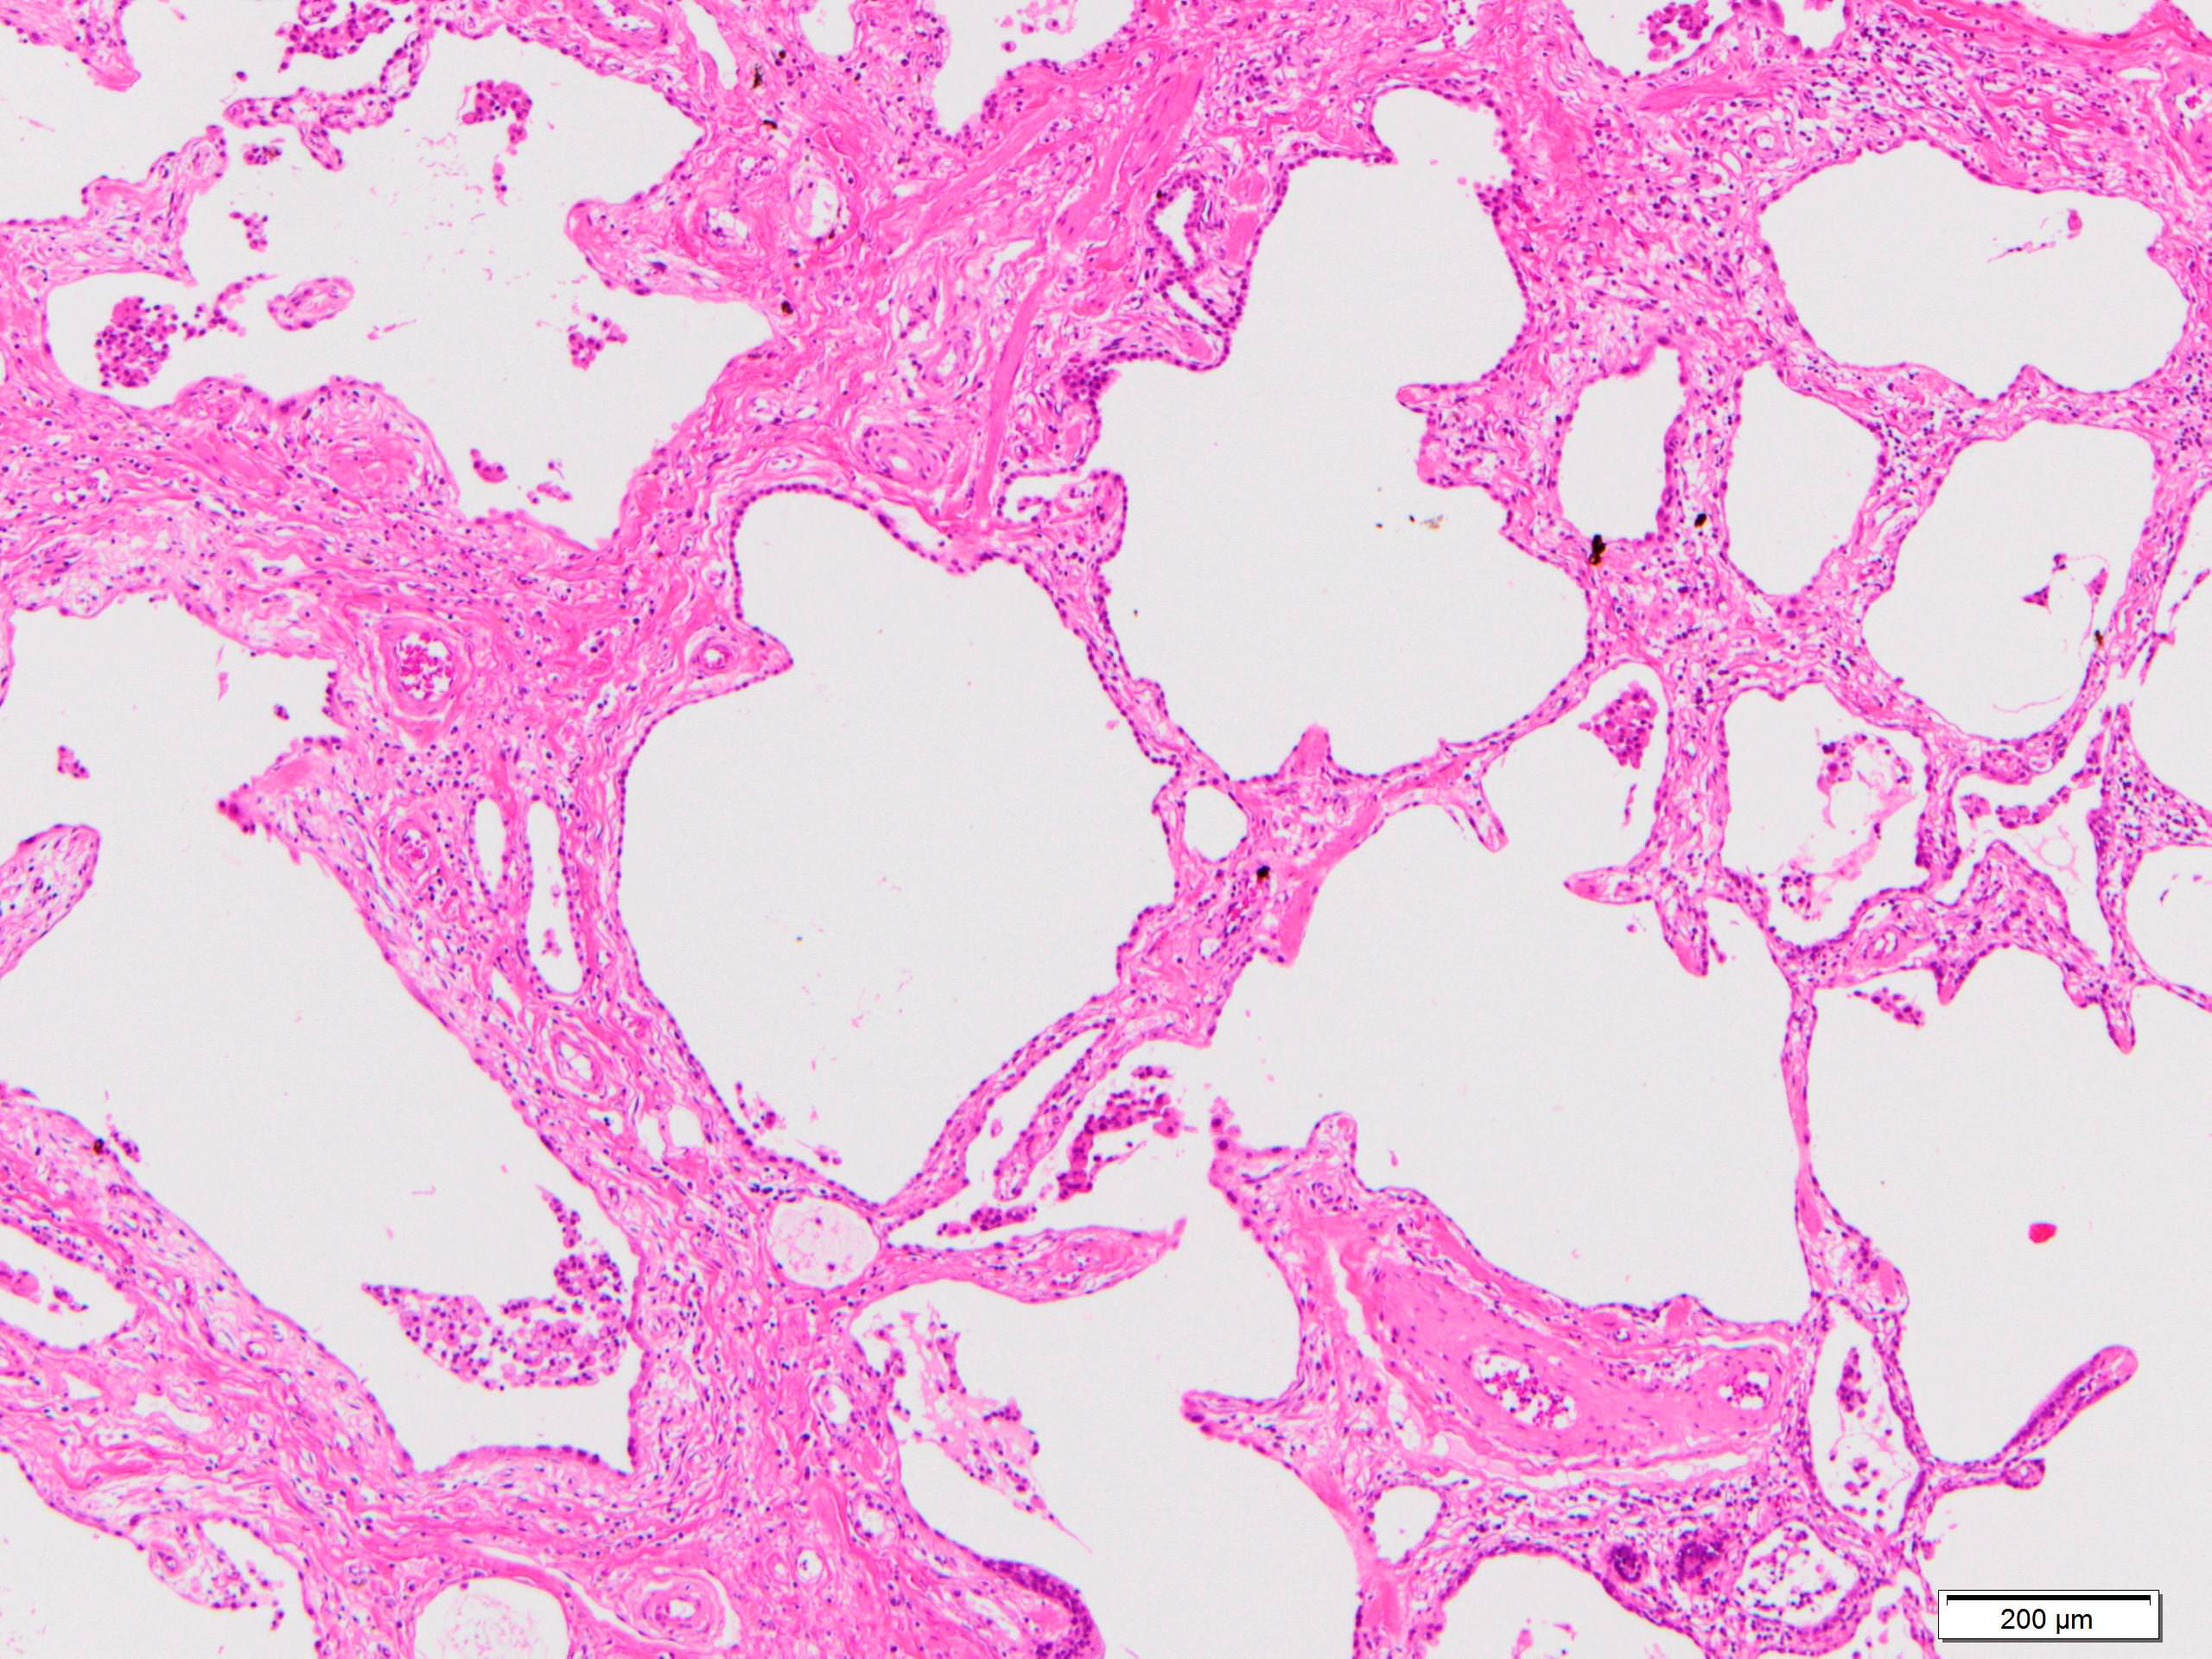

Microscopic (histologic) description

- Since there are few specific findings for NSIP pattern, it is essential to exclude other lung diseases on histology (Am J Respir Crit Care Med 2008;177:1338)

- Characteristic findings of NSIP pattern

- Diffuse and uniform inflammation ("temporal homogeneity") on low power of alveolar wall, bronchovascular bundles and pleura

- There are usually no normal alveolar walls in the affected lobules

- Cellular or fibrotic change

- Lymphocytic or plasmacytic infiltration

- Loose fibrosis

- Lung architecture is frequently preserved

- "Cellular NSIP" or "fibrotic NSIP" can be stated specifically in pathologist report

- Diffuse and uniform inflammation ("temporal homogeneity") on low power of alveolar wall, bronchovascular bundles and pleura

Microscopic (histologic) images

Scroll to see all images.

Contributed by Akira Yoshikawa, M.D.

Images hosted on other servers:

Contributed by Akira Yoshikawa, M.D.

Images hosted on other servers: